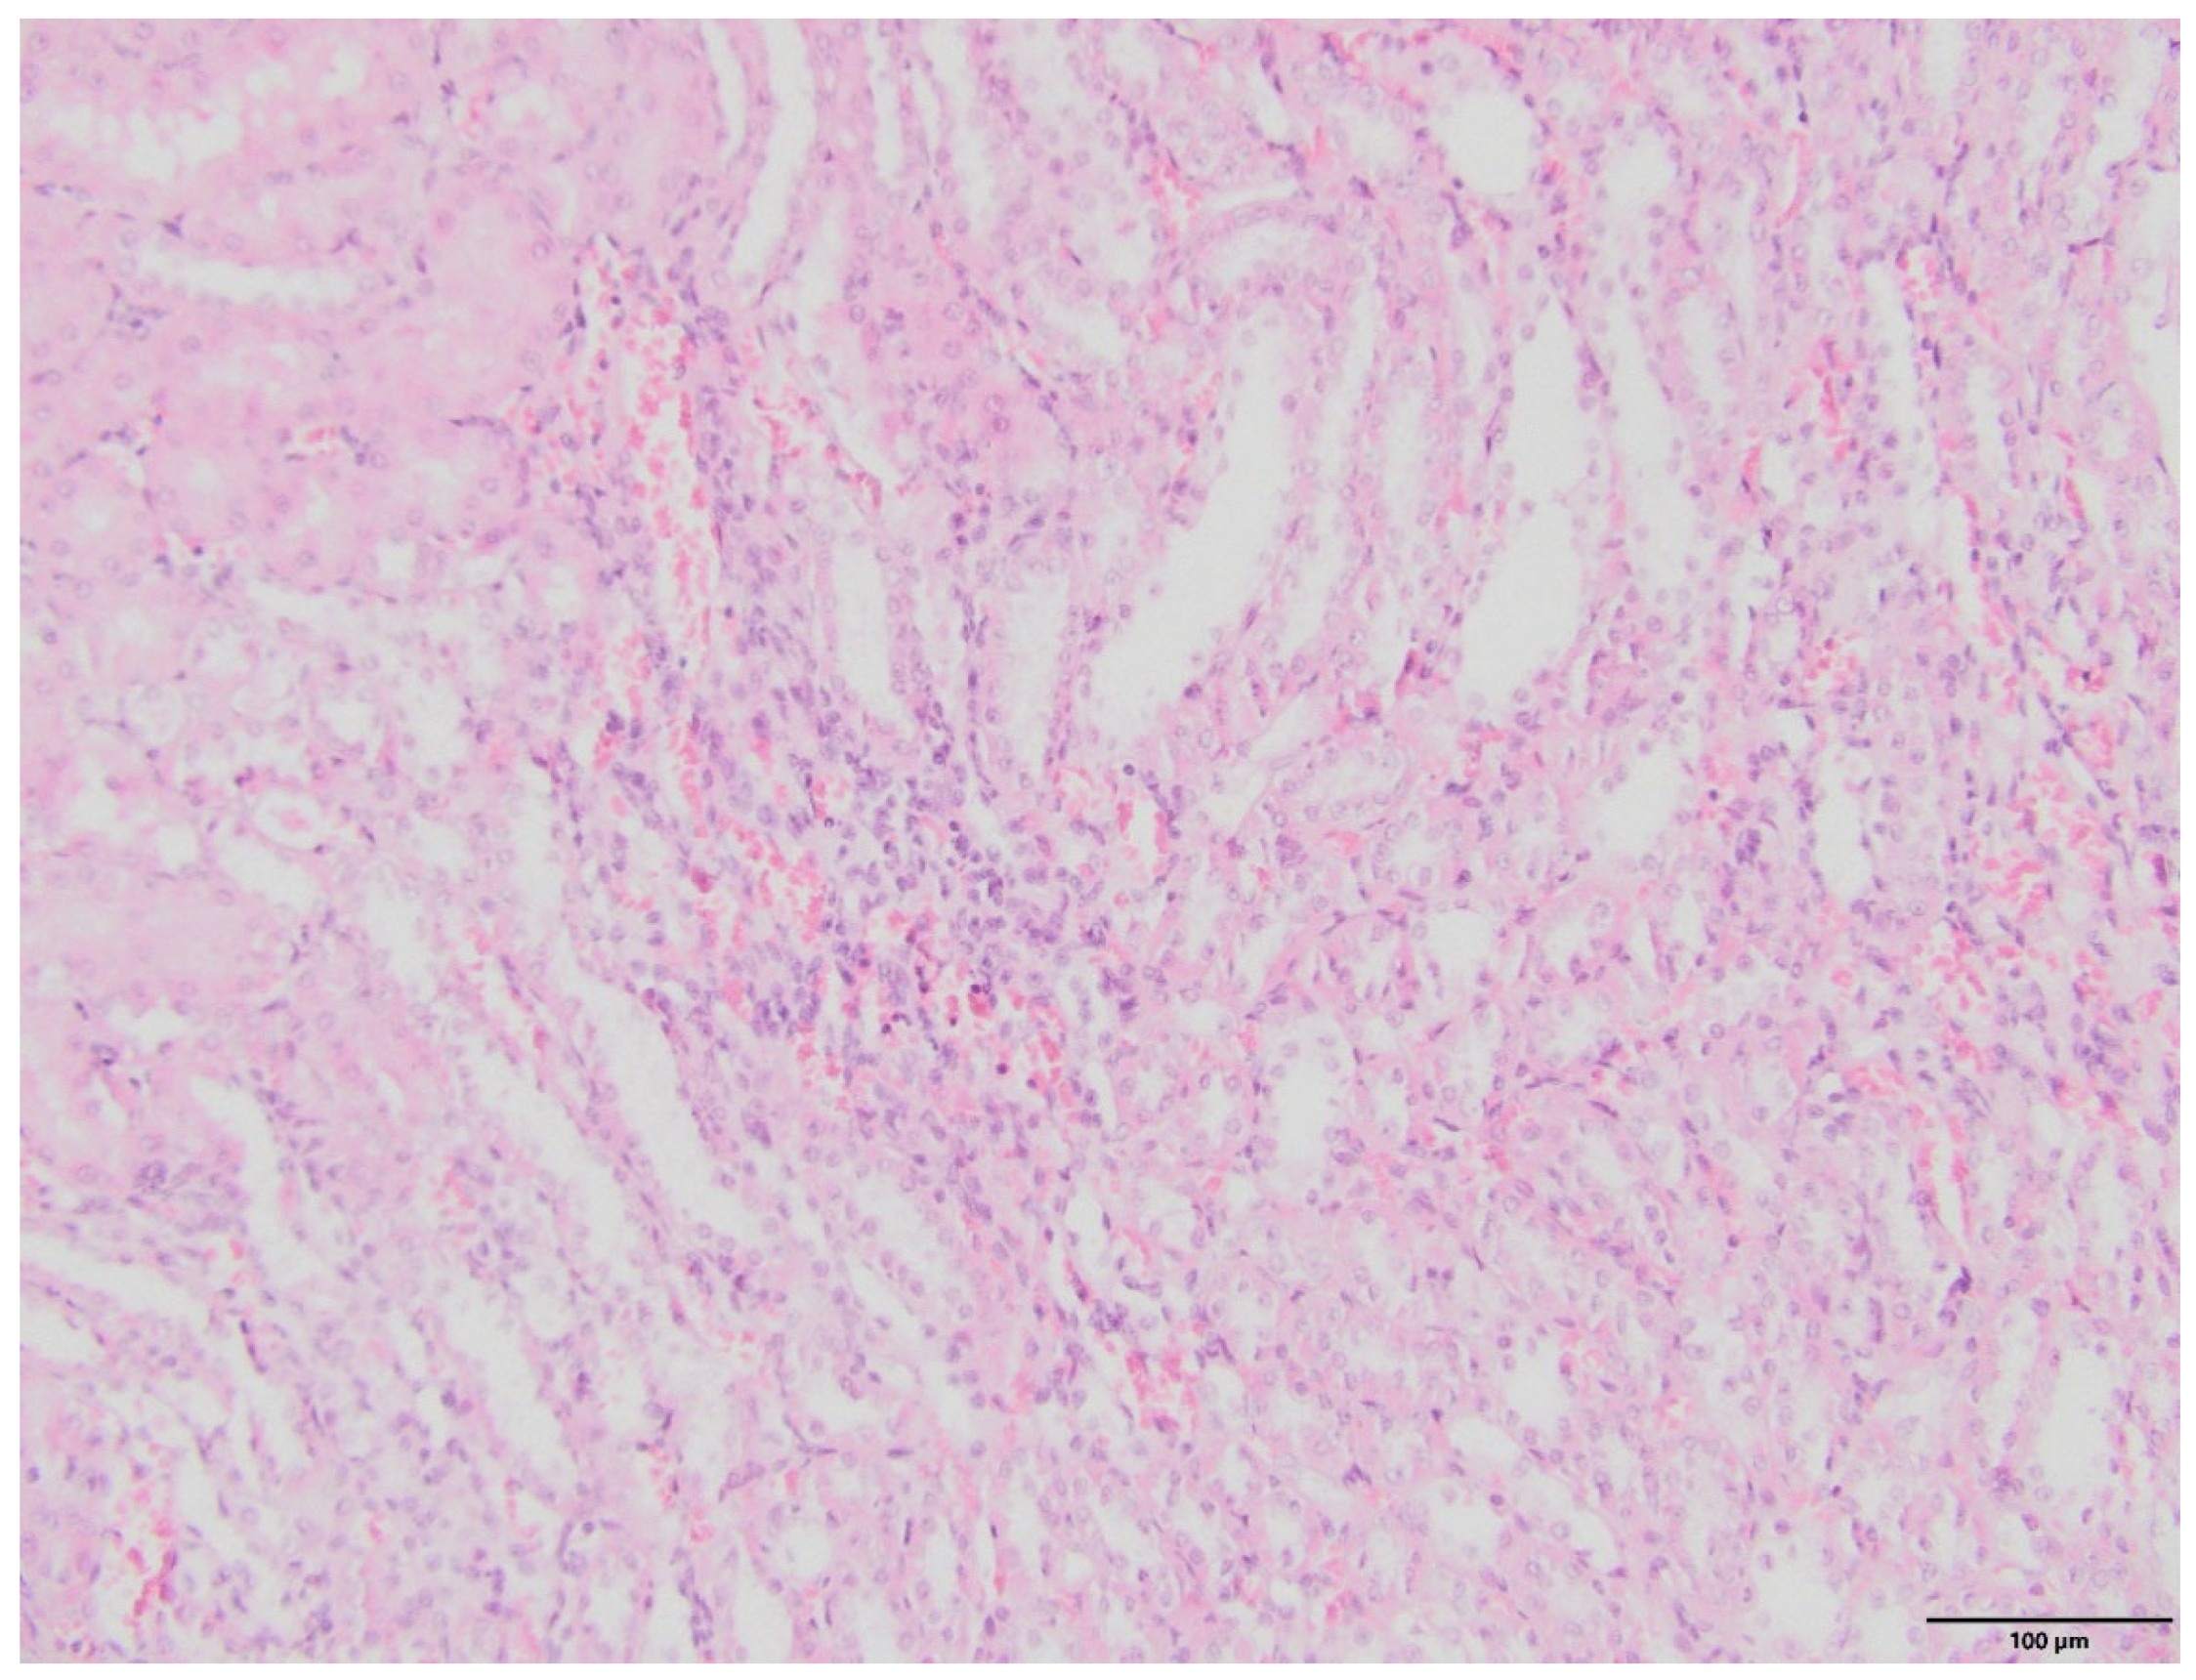

2.4. Kidney Histopathology